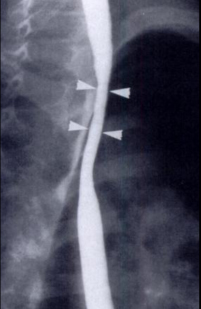

Oesophagite caustique 1/3 moyen de

oesophage avec aspect lesionaire c'est imsage

stenose cicatricielle a bord lisse de perdre

elasticite ( fleche blanche ) |